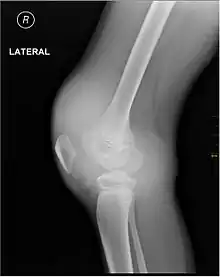

Muscle and joint haemorrhages – or haemarthrosis – are indicative of haemophilia,[7] while digestive tract and cerebral haemorrhages are also germane to other coagulation disorders. Though typically not life-threatening, joint bleeding is one of the most serious symptoms of haemophilia. Repeated bleeds into a joint capsule can cause permanent joint damage and disfigurement resulting in chronic arthritis and disability. Joint damage is not a result of blood in the capsule but rather the healing process. When blood in the joint is broken down by enzymes in the body, the bone in that area is also degraded, this exerts a lot of pain upon the person affected by the disease.